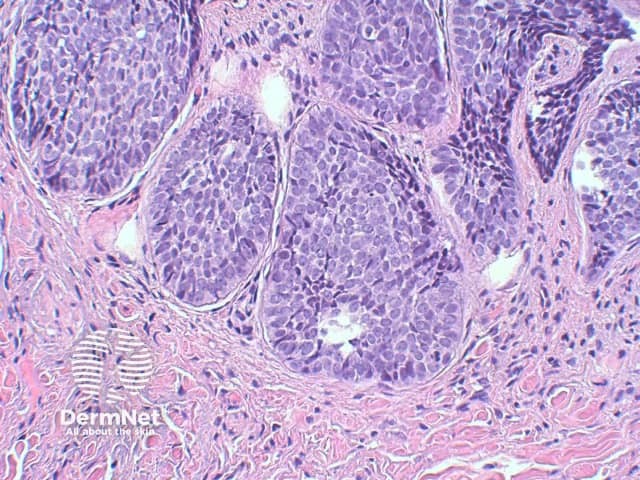

The key feature of basal cell carcinoma at low power magnification is of a basaloid epithelial tumour arising from the epidermis (figure 1). The basaloid epithelium typically forms a palisade with a cleft forming from the adjacent tumour stroma (figure 2). Centrally the nuclei become crowded with scattered mitotic figures and necrotic bodies evident (figure 3). A useful distinguishing feature from other basaloid cutaneous tumours is the presence of a mucinous stroma (figure 4). Some tumours may also show foci of regression, seen as areas of eosinophilic stroma with lack of basaloid nests.

Figure 3